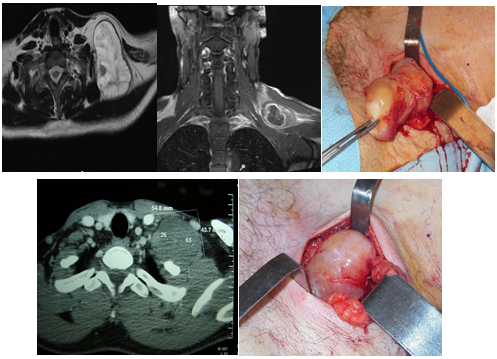

Two tumors were located at the supraclavicular fossa. The way of presentation of them was a tumor at the region of the neck. They were studied by tomography and MRI. The fine needle aspiratorion was non-especific. They were completely resected by a cervical approach. The possible nerves of origin were branches of the cervical sympathetic chain. There was no post operatory neurological deficit. There were no recurrences during the follow-up (5 years) (Figure 7).

Figure 7 Solitary neurofibroma (above), and neurilemoma (below), originated at branches of the cervical sympathetic chain. Complete resection.